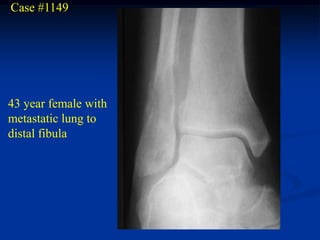

Case #1149

43 year female with

metastatic lung to

distal fibula